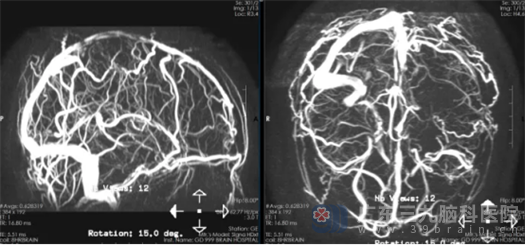

鲁明副院长、神经外五科副主任卢建侃带领神经外五科医疗团队迅速阅片讨论。为抢救患者的生命,急诊行脑血管造影+颅内静脉窦取栓术。术中,取出大量混合血栓,复查造影见上矢状窦复通,局部管腔欠光滑,静脉滞留较前明显好转。手术顺利结束。